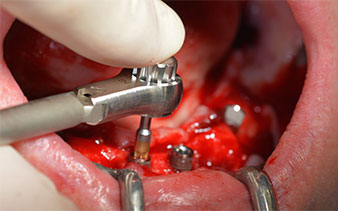

Die nächste programmierte Einstellung ist bereits die Implantateinbringung. Die Implantate werden in unserem Hause standardmäßig mit einer Kraft von 32Ncm inseriert (Abb. 12 und 13).

Die absolute Voraussetzung für die Sofortversorgung ist die hohe Primärstabilität. Um diese zu erfüllen, wurde in diesem Fall auf ein Gewindeschneiden verzichtet. Die hier verwendete Antriebseinheit Implantmed von W&H besitzt hierfür einen eigenen Modus, der ebenfalls direkt anwählbar und für viele Indikationen unverzichtbar ist. Die letzten Umdrehungen bei der Implantateinbringung überschritten den Wert von 32Ncm und wurden manuell durchgeführt. Hierfür empfiehlt es sich, die Selbstschneidefunktion der Implantate auszunutzen und das Implantat mehrmals vorwärts und rückwärts zu drehen. So gelangt das Implantat schrittweise näher bis zur endgültigen Position, ohne zu starken Druck auf den Knochen auszuüben (Abb. 14).